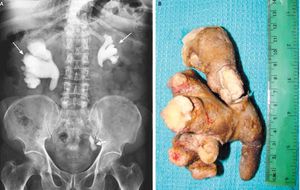

A 58-year-old man presented with a 1-year history of dysuria. His medical history was notable for recurrent pyelonephritis on the right side. Evaluation at this time revealed staghorn calculus (Panel A, long arrows) and left ureteric calculus (Panel A, short arrow), with mild renal failure (serum creatinine level, 2.1 mg per deciliter [186 μmol per liter]). A urine culture was positive for Escherichia coli. Renal scanning with the use of 99mTc-labeled diethylenetriamine pentaacetic acid (DTPA) showed that both kidneys were functioning, with the right kidney performing more efficiently than the left. After renal function was optimized by means of percutaneous nephrostomy and treatment with antibiotics, the patient underwent extended pyelolithotomy of the right kidney (the extracted staghorn calculus is shown in Panel B). After surgery, renal function improved and has since remained stable (serum creatinine level, 1.3 mg per deciliter [115 μmol per liter]), and the symptoms of painful urination abated. Percutaneous nephrolithotomy and ureteroscopic lithotripsy on the left side are planned for future treatment. Staghorn calculus may be associated with recurrent urinary tract infections and renal failure. Shanmugasundaram Rajaian, M.D. Nitin Sudhakar Kekre, M.D. Christian Medical College, Vellore, India